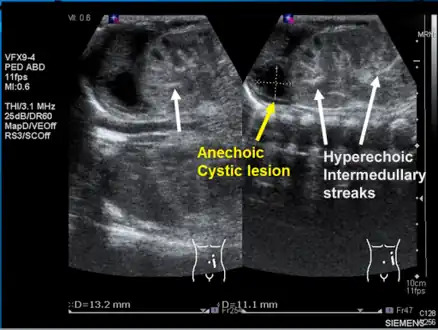

Left kidney with a suprarenal anechoic cyst-like lesion and hyperechoic intermedullary streaks in initial phase of renal vein thrombosis

Left kidney with a suprarenal anechoic cyst-like lesion and hyperechoic intermedullary streaks in initial phase of renal vein thrombosis CT showing dilatation and thrombosis of the left renal vein in a patient with nutcracker syndrome